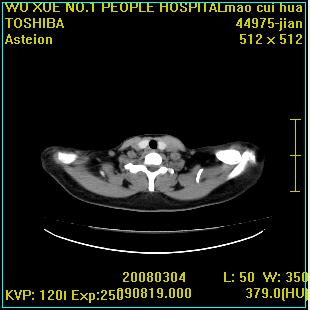

标题: CT12025:男,50岁,左肩活动受限半年。 [打印本页]

标题: CT12025:男,50岁,左肩活动受限半年。

肩关节骨质破坏呈小囊状,其周软组织轻度肿胀,余未见异常。

考虑:肩袖损伤。建议mri。

左侧肱骨头密度不均匀,高低混杂,周围软组织略肿胀,考虑结核性病变。

考虑左侧肱骨慢性骨髓炎。

左侧肱骨头密度不均匀,高低混杂,髓腔密度稍高,周围软组织略肿胀,肌间隙模糊,考虑慢性骨髓炎可能。密切结合临床!